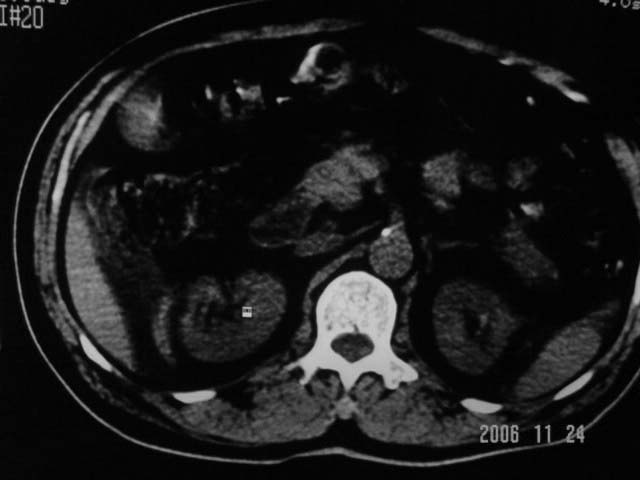

劳烦各位老师看一下最后一幅箭头指的地方是不是胆总管结石.ct值约63hu.

胆总管内结节状高密度灶,边缘隐约可见低密度环绕,首先考虑结石伴肝内胆管扩张; 2、胆囊增大,胆囊炎

胆总管下端结石

支持胆总管下段结石并肝内外胆管扩张。

1.肝内外胆管扩张,楼主箭头所示处多系结石.

是结石伴梗阻.

楼主的箭头标的太棒了,不看最后一副图,我都没看到胆管下端有问题,象结石